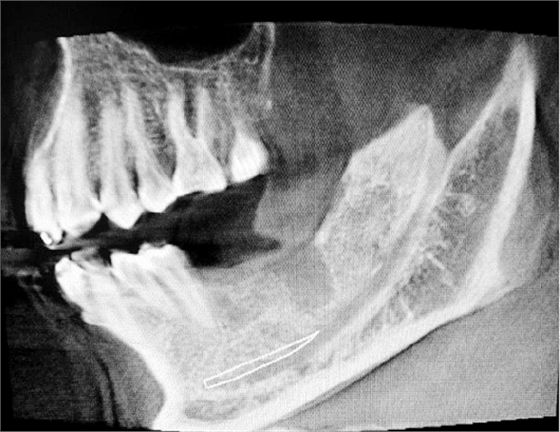

左下67缺失